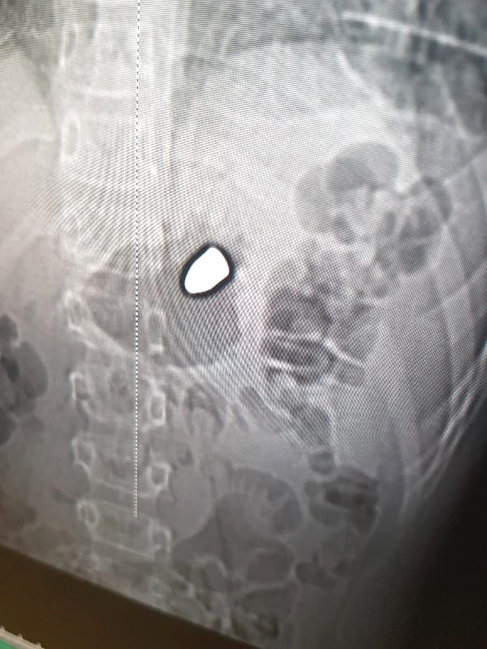

Belə ki, kimliyi bilinməyən şəxs tərəfindən açılan atəş nəticəsində Arda Şeyhanlıgil ürəyindən yaralanıb.